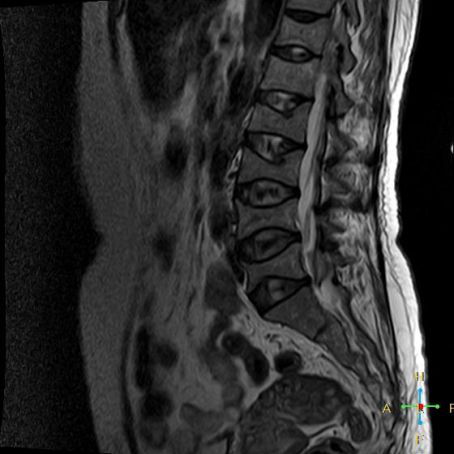

2 良性压缩性骨折 椎体形态:楔形、凹陷形。 椎体连续性病变(骨质疏松):新鲜、陈旧骨折并存。

椎间盘改变:椎间盘增厚呈双凸透镜状, 椎间盘疝入椎体, 形成许莫氏结节。

椎体后上角或后下角向后翘起, 呈尖突样突入椎管, 具有特异性,为其它原因的骨折所少见。

——良性压缩性骨折MR信号特点—— 良性骨折的修复过程:缺血性变化--修复(骨髓水肿、血流增加或充血现象)--修复近完成(血流恢复正常)--慢性期(脂肪组织再生)。 正常成人:椎体为黄骨髓,T1WI 、T2WI 均为高信号。 当骨髓内出现水肿时,T1 低信号, 与残余的正常骨髓形成明显对比,所以椎体压缩骨折后,MR 信号改变以 T1WI 上观察最好;而在常规 T2WI 图像上,病变骨髓的长 T2 高信号与正常骨髓脂肪信号差别较小,不易观察;T2WI 脂肪抑制技术对于突出显示骨折区长 T2 组织信号具有独特优势,对于判断椎体是否发生脂肪变及骨折是否愈合也有一定价值。 急性早期,椎体压缩,局部缺血,骨髓水肿,T1WI 不均匀低信号,T2WI 高信号,增强扫描无明显的强化。 随后,骨折部位开始修复,血流量增加,增强扫描可出现明显的强化,平扫信号无改变。 慢性期,骨髓内脂肪组织再生,T1WI 椎体内呈混杂高信号。

由于大多数外力轻微,椎体内多形成范围局限、移位不明显的骨折线,骨折线周围水肿亦多局限,因此,较少出现全椎体信号异常。

椎体后角回避现象:T1WI 椎体上部或大部呈低信号, 而后角信号不变。